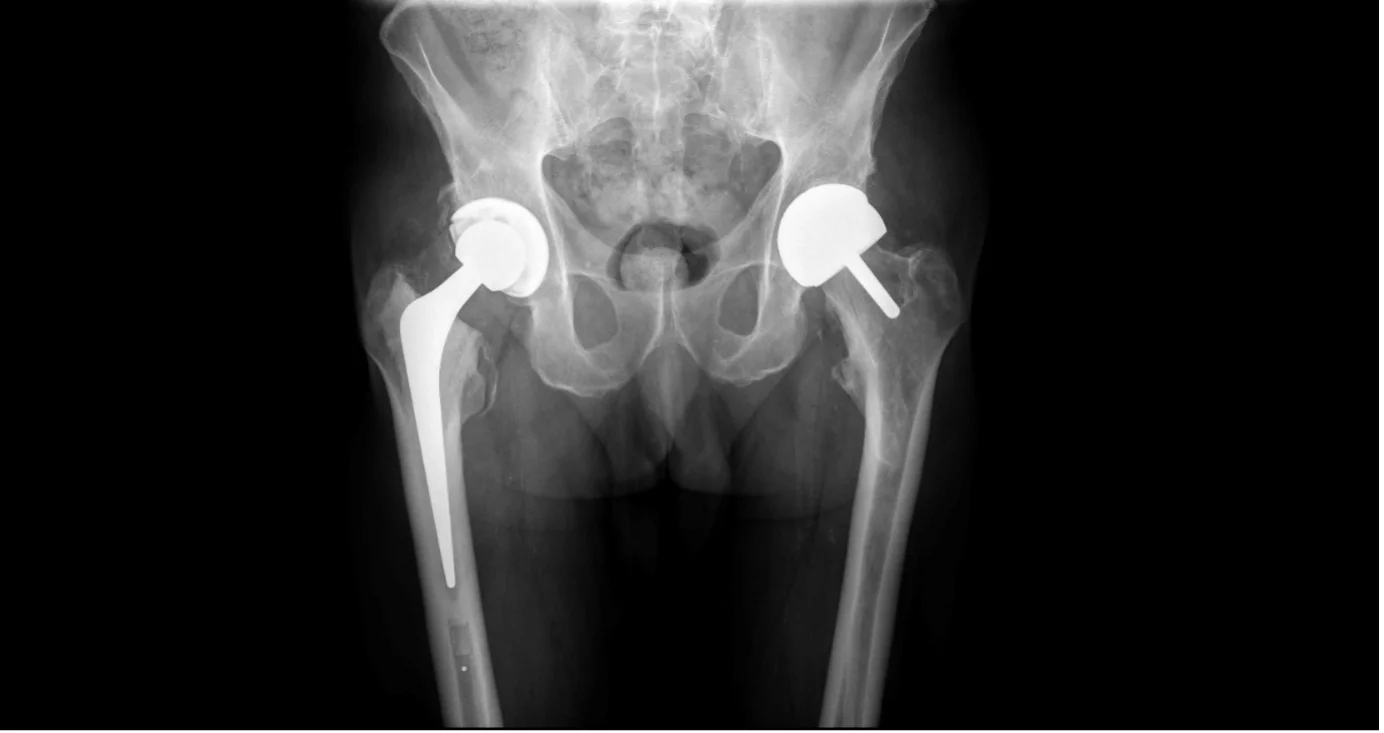

Surgical Images & X-rays

Hip resurfacing is a surgical procedure that treats hip arthritis while preserving significantly more of your natural bone than a traditional total hip replacement. Instead of removing the entire femoral head (the ball of the hip joint), it is reshaped and capped with a smooth metal or ceramic covering. The damaged hip socket is also resurfaced with a matching shell.

Because the natural bone structure is preserved, the replacement closely matches the size and mechanics of your original hip. This results in a more stable joint with a lower risk of dislocation, and makes any future revision surgery — should it ever be needed — significantly easier.

Mr Hussain selects the most appropriate implant for each patient based on their anatomy, bone quality, activity goals, and gender. He is one of few UK surgeons offering both metal-on-metal and ceramic-on-ceramic resurfacing options.

A proven metal-on-metal resurfacing system with excellent long-term results. Used primarily in male patients with adequate femoral head size. Well-established track record with robust clinical evidence.